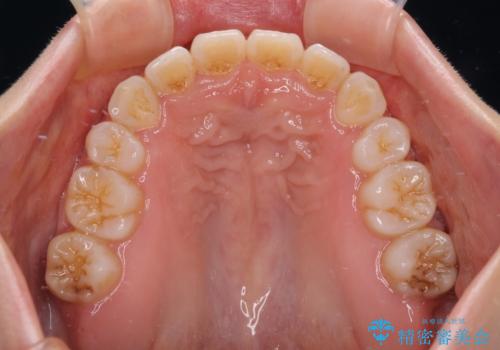

- 前歯が突出しているために口が閉じられないとのことで来院された患者様です。

上下ともに顎が小さく、歯列が前方に突き出していたため、上下左右の第一小臼歯4本を抜歯し、口元の突出感を改善していくこととしました。